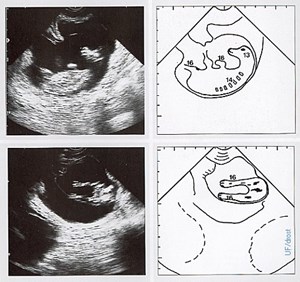

Bovine fetus at 59 days of pregnancy.  Transrectal ultrasonograms (left) of the fetus within the uterus, and explanatory diagrams (right) of the ultrasonograms; lateral view (top) and rear view (bottom). The amnionic vesicle becomes less turgid at this stage of pregnancy, permitting the fetus to be identified by palpation per rectum. The fetus was about the size of a mouse. Legend; 13 = head, 14 = trunk, 16 = limbs.  This image is related to NAL #2296, 2298, 2299, and 2300.

Description: Bovine fetus at 59 days of pregnancy. Transrectal ultrasonograms (left) of the fetus within the uterus, and explanatory diagrams (right) of the ultrasonograms; lateral view (top) and rear view (bottom). The amnionic vesicle becomes less turgid at this stage of pregnancy, permitting the fetus to be identified by palpation per rectum. The fetus was about the size of a mouse. Legend; 13 = head, 14 = trunk, 16 = limbs. This image is related to NAL #2296, 2298, 2299, and 2300.